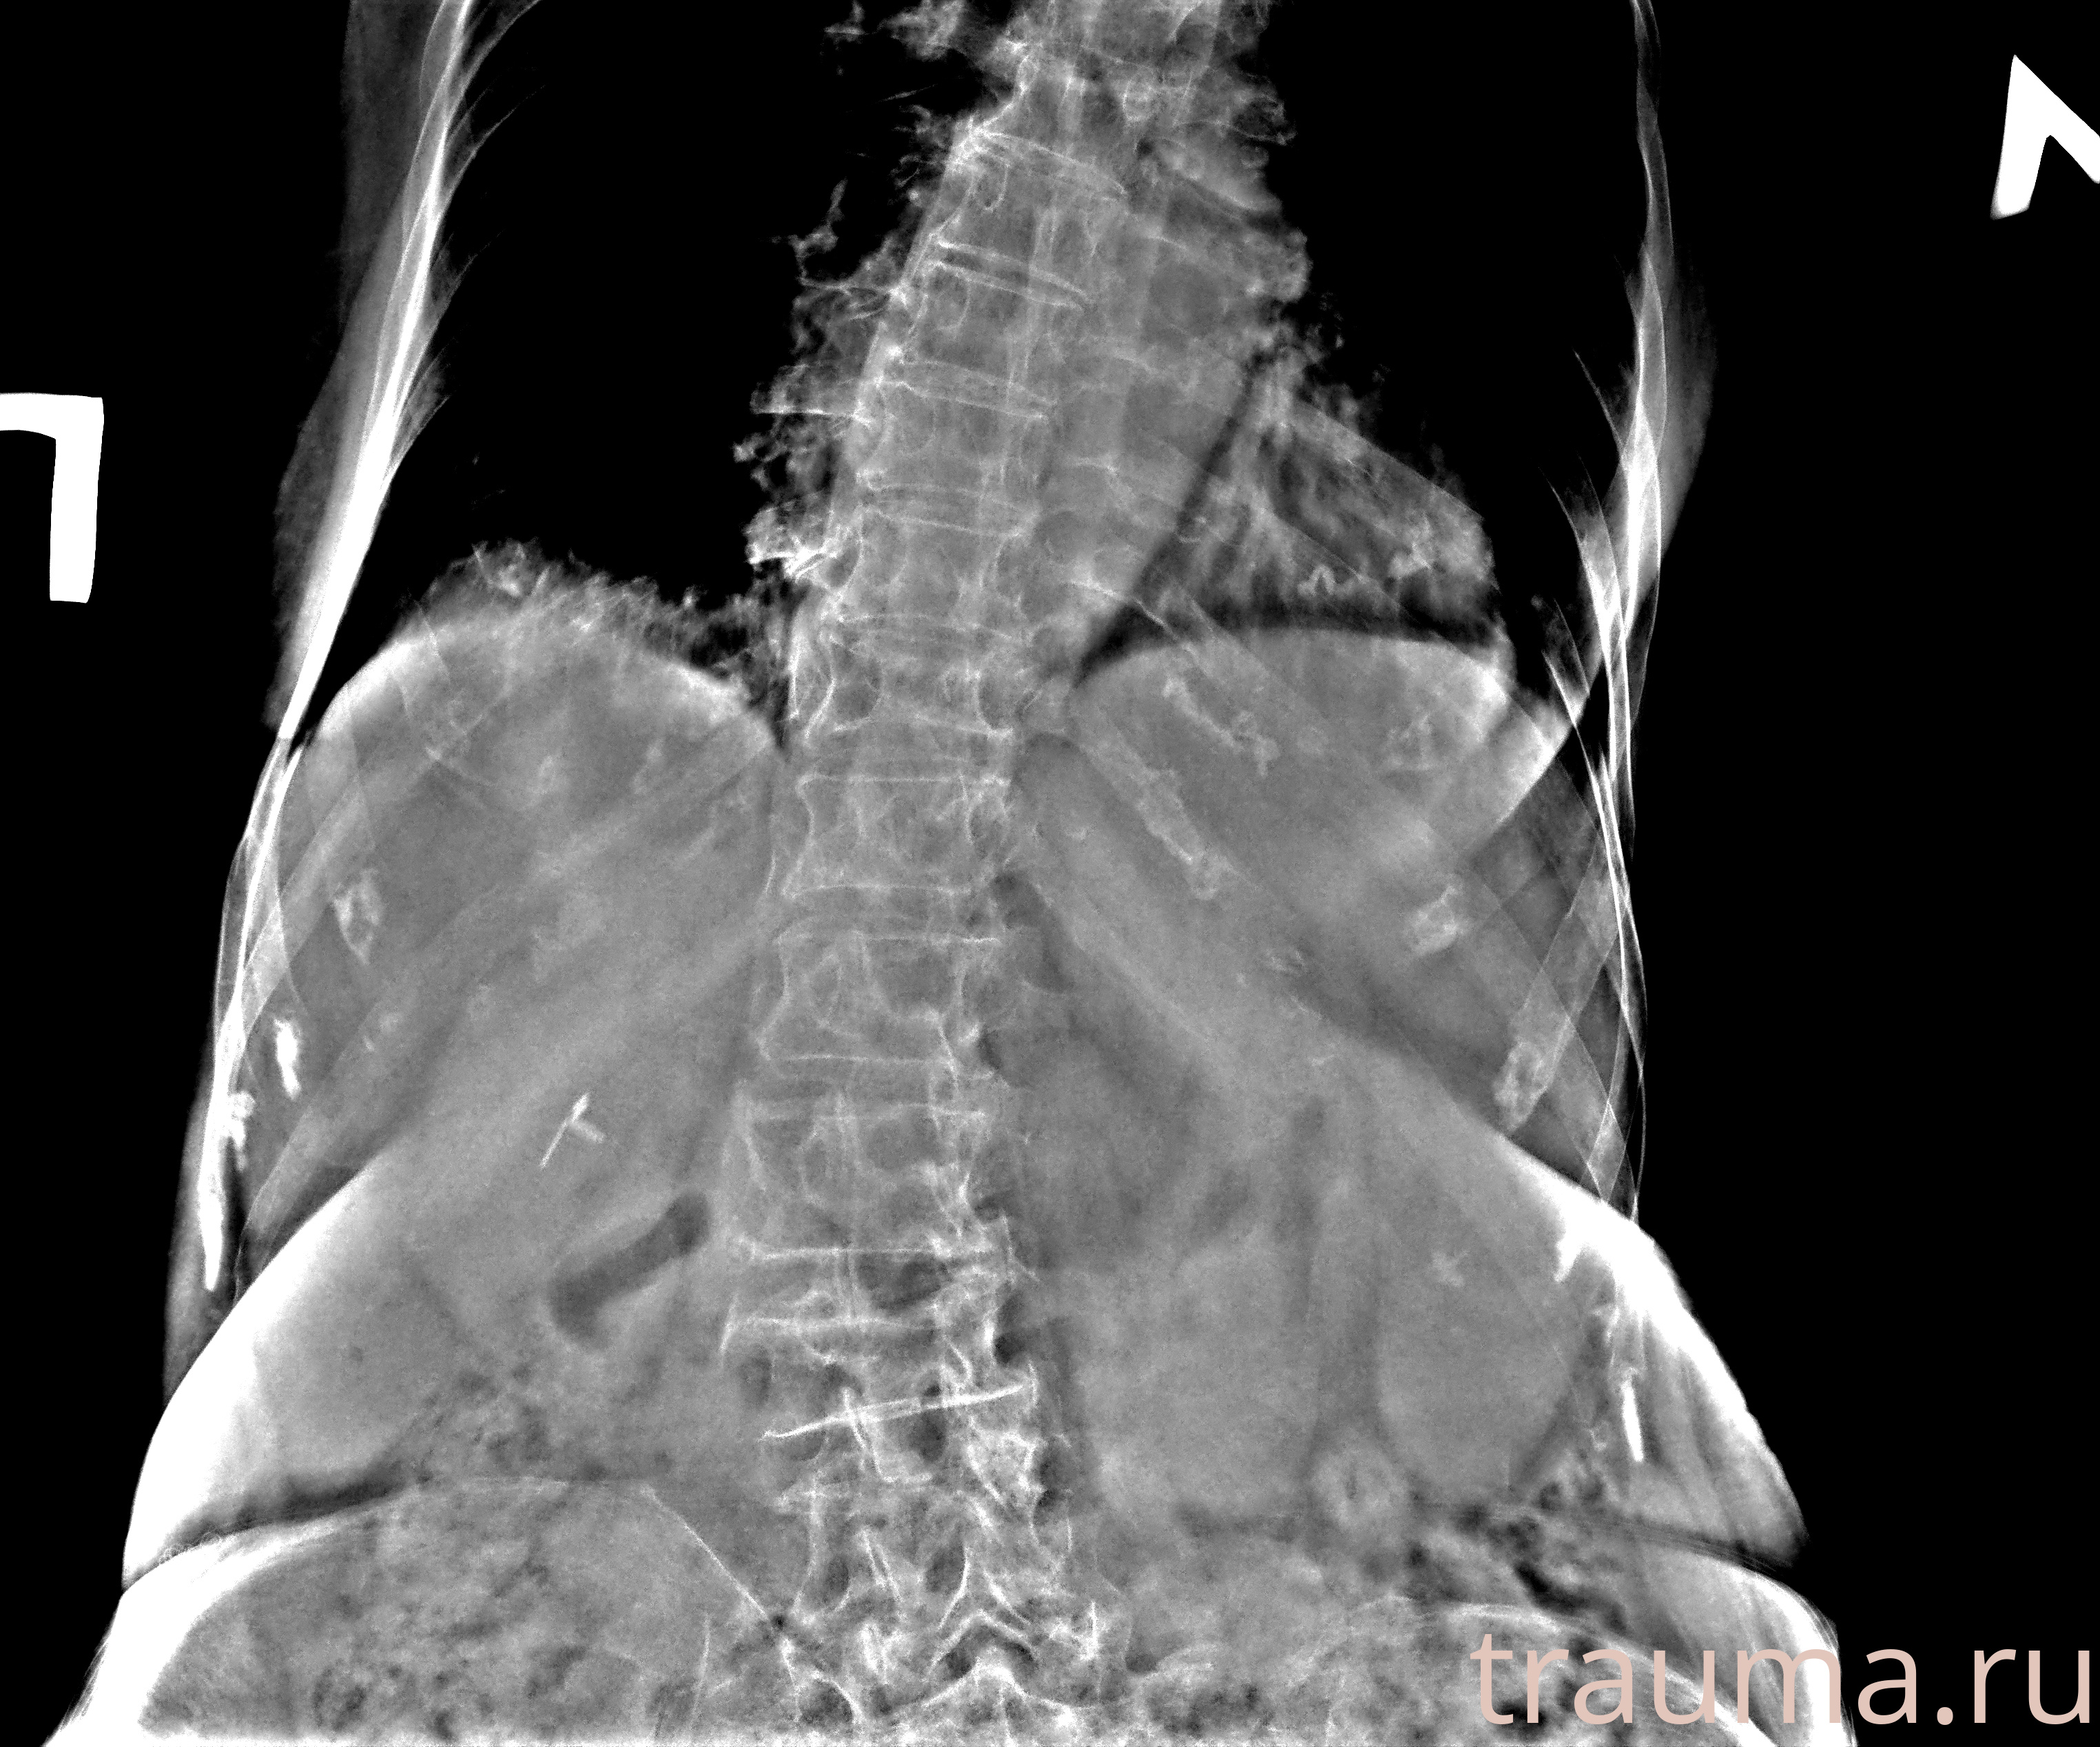

Рентген на дому: по вашему адресу приезжает врач-рентгенолог, травматолог-ортопед с мобильным рентгеновским аппаратом, проводит диагностику травмы или заболевания, делает необходимые рентгенограммы, дает рекомендации по дальнейшему лечению. Получить качественные снимки в домашних условиях возможно благодаря уникальной методике, разработанной МосРентген Центром для института  Склифосовского